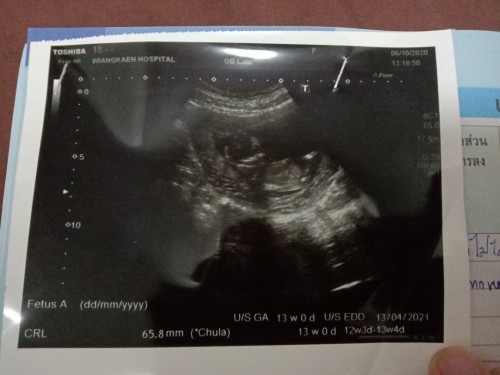

ขอถามหน่อยค่ะ เด็กน้ำหนักตามเกณฑ์มั้ยคะ13วีคค่ะ